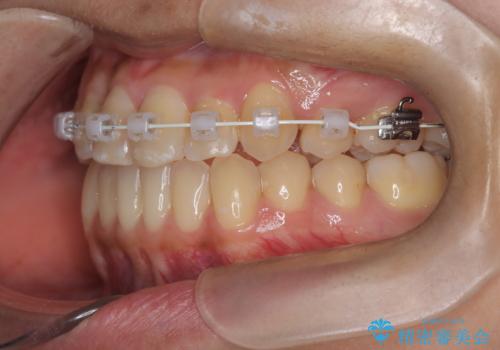

- 患者様は左上の八重歯を気にされて来院されました。八重歯による歯列の乱れだけでなく、翼状捻転(歯がねじれるように生えている状態)も見られました。目立たない矯正を希望されていたため、**インビザライン(マウスピース矯正)**を選択し、左上の小臼歯を抜歯してスペースを作りながら歯を並べる治療計画を立てました。しかし、治療の途中で翼状捻転の改善が十分に進まなかったため、患者様の希望も踏まえ、上顎のみワイヤー矯正に変更することとなりました。

治療開始時はインビザラインを使用し、全体の歯並びを整えながら抜歯スペースを活用して歯を後方へ移動させました。しかし、左上の八重歯のねじれが強く、マウスピースのみでは十分にコントロールできないことが判明。そこで、より細かく歯を動かすために上顎のみワイヤー矯正へ切り替えました。ワイヤー矯正によって翼状捻転も改善し、最終的にバランスの取れた歯並びと噛み合わせを実現。患者様からは「長い治療だったけれど、しっかり整って満足」と嬉しいお言葉をいただきました。